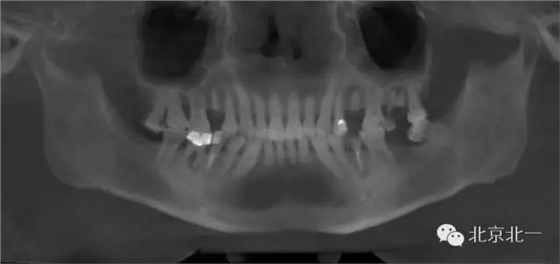

1.難度預(yù)判:拔牙前了解需拔除患牙情況及其與鄰牙、周圍組織的關(guān)系 術(shù)前影像學(xué)檢查了解牙齒形態(tài)、結(jié)構(gòu)及其與周圍重要解剖結(jié)構(gòu),如上頜竇、下頜神經(jīng)管等的位置關(guān)系。術(shù)前與患者及家屬交代拔牙過程及術(shù)中、術(shù)后的相關(guān)事項(xiàng),以緩解患者的緊張、恐懼心理,取得其信任與配合。

分享BENEX微創(chuàng)工具拔牙一例:

總結(jié):一、器械非常高大上,價格昂貴,能夠避免傳統(tǒng)拔牙方式最骨造成擠壓傷。此器械通過牽引的方式來拔除殘根,

二、單純用此器械可能會效果不佳,需要配合其他微創(chuàng)拔牙刀(例如雅典刀)先進(jìn)行切割牙周膜,再通過牽引把牙微創(chuàng)拔除效果更好。